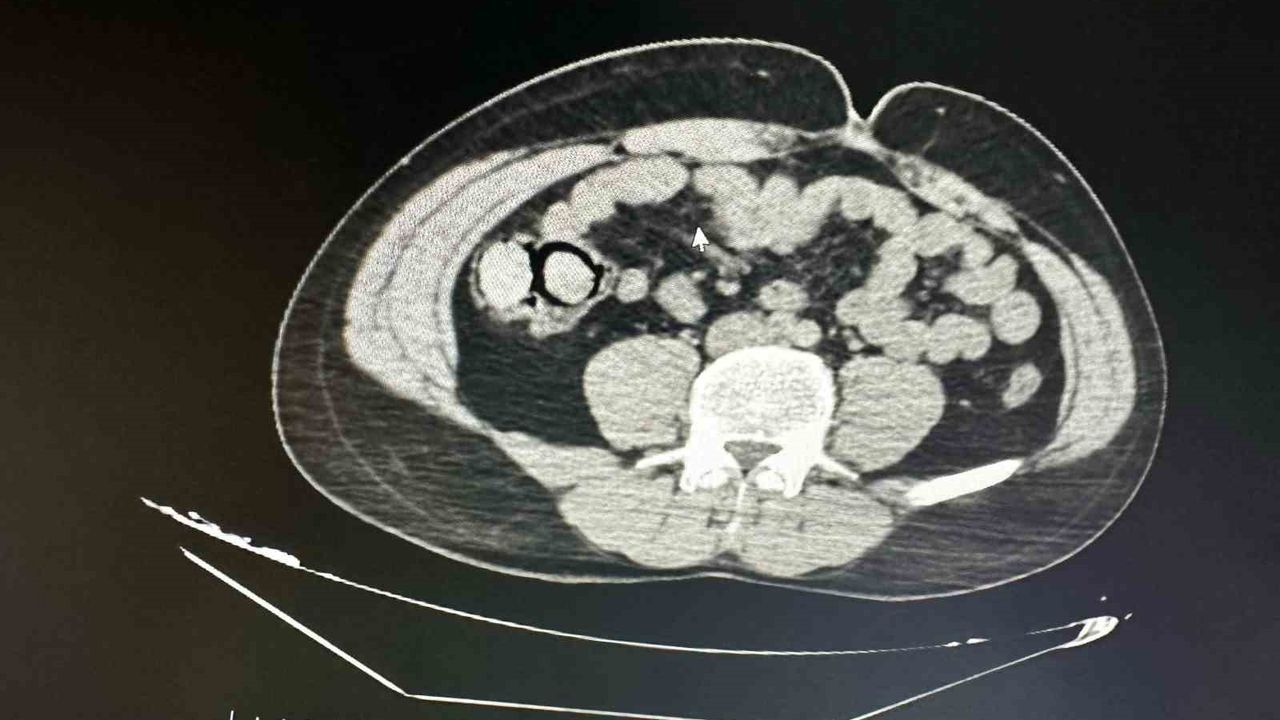

Bingöl’de akıllara durgunluk veren bir olay gerçekleşti. Otobüs yolculuğu sırasında polis ekiplerince durdurulan yabancı uyruklu iki şahsın midesinden 10 parça halinde 113 gram metamfetamin çıktı.

Bingöl Emniyet Müdürlüğü Narkotik Suçlarla Mücadele Şube Müdürlüğüne bağlı narko-timleri akıllara durgunluk veren bir uyuşturucu kaçakçılığını çözdü. Ekiplerin çalışmaları neticesinde otobüs ile Bingöl’e gelen şüpheli yabancı uyruklu 2 şahsın iç beden muayenesinde 10 parça halinde 113 gram metamfetamin maddesi tespit edildi. Emniyetteki işlemlerinin ardından mahkemeye çıkarılan 2 şahıs, uyuşturucu madde ticareti yapmak suçundan tutuklanarak Elazığ Kapalı ceza infaz kurumuna teslim edildi.